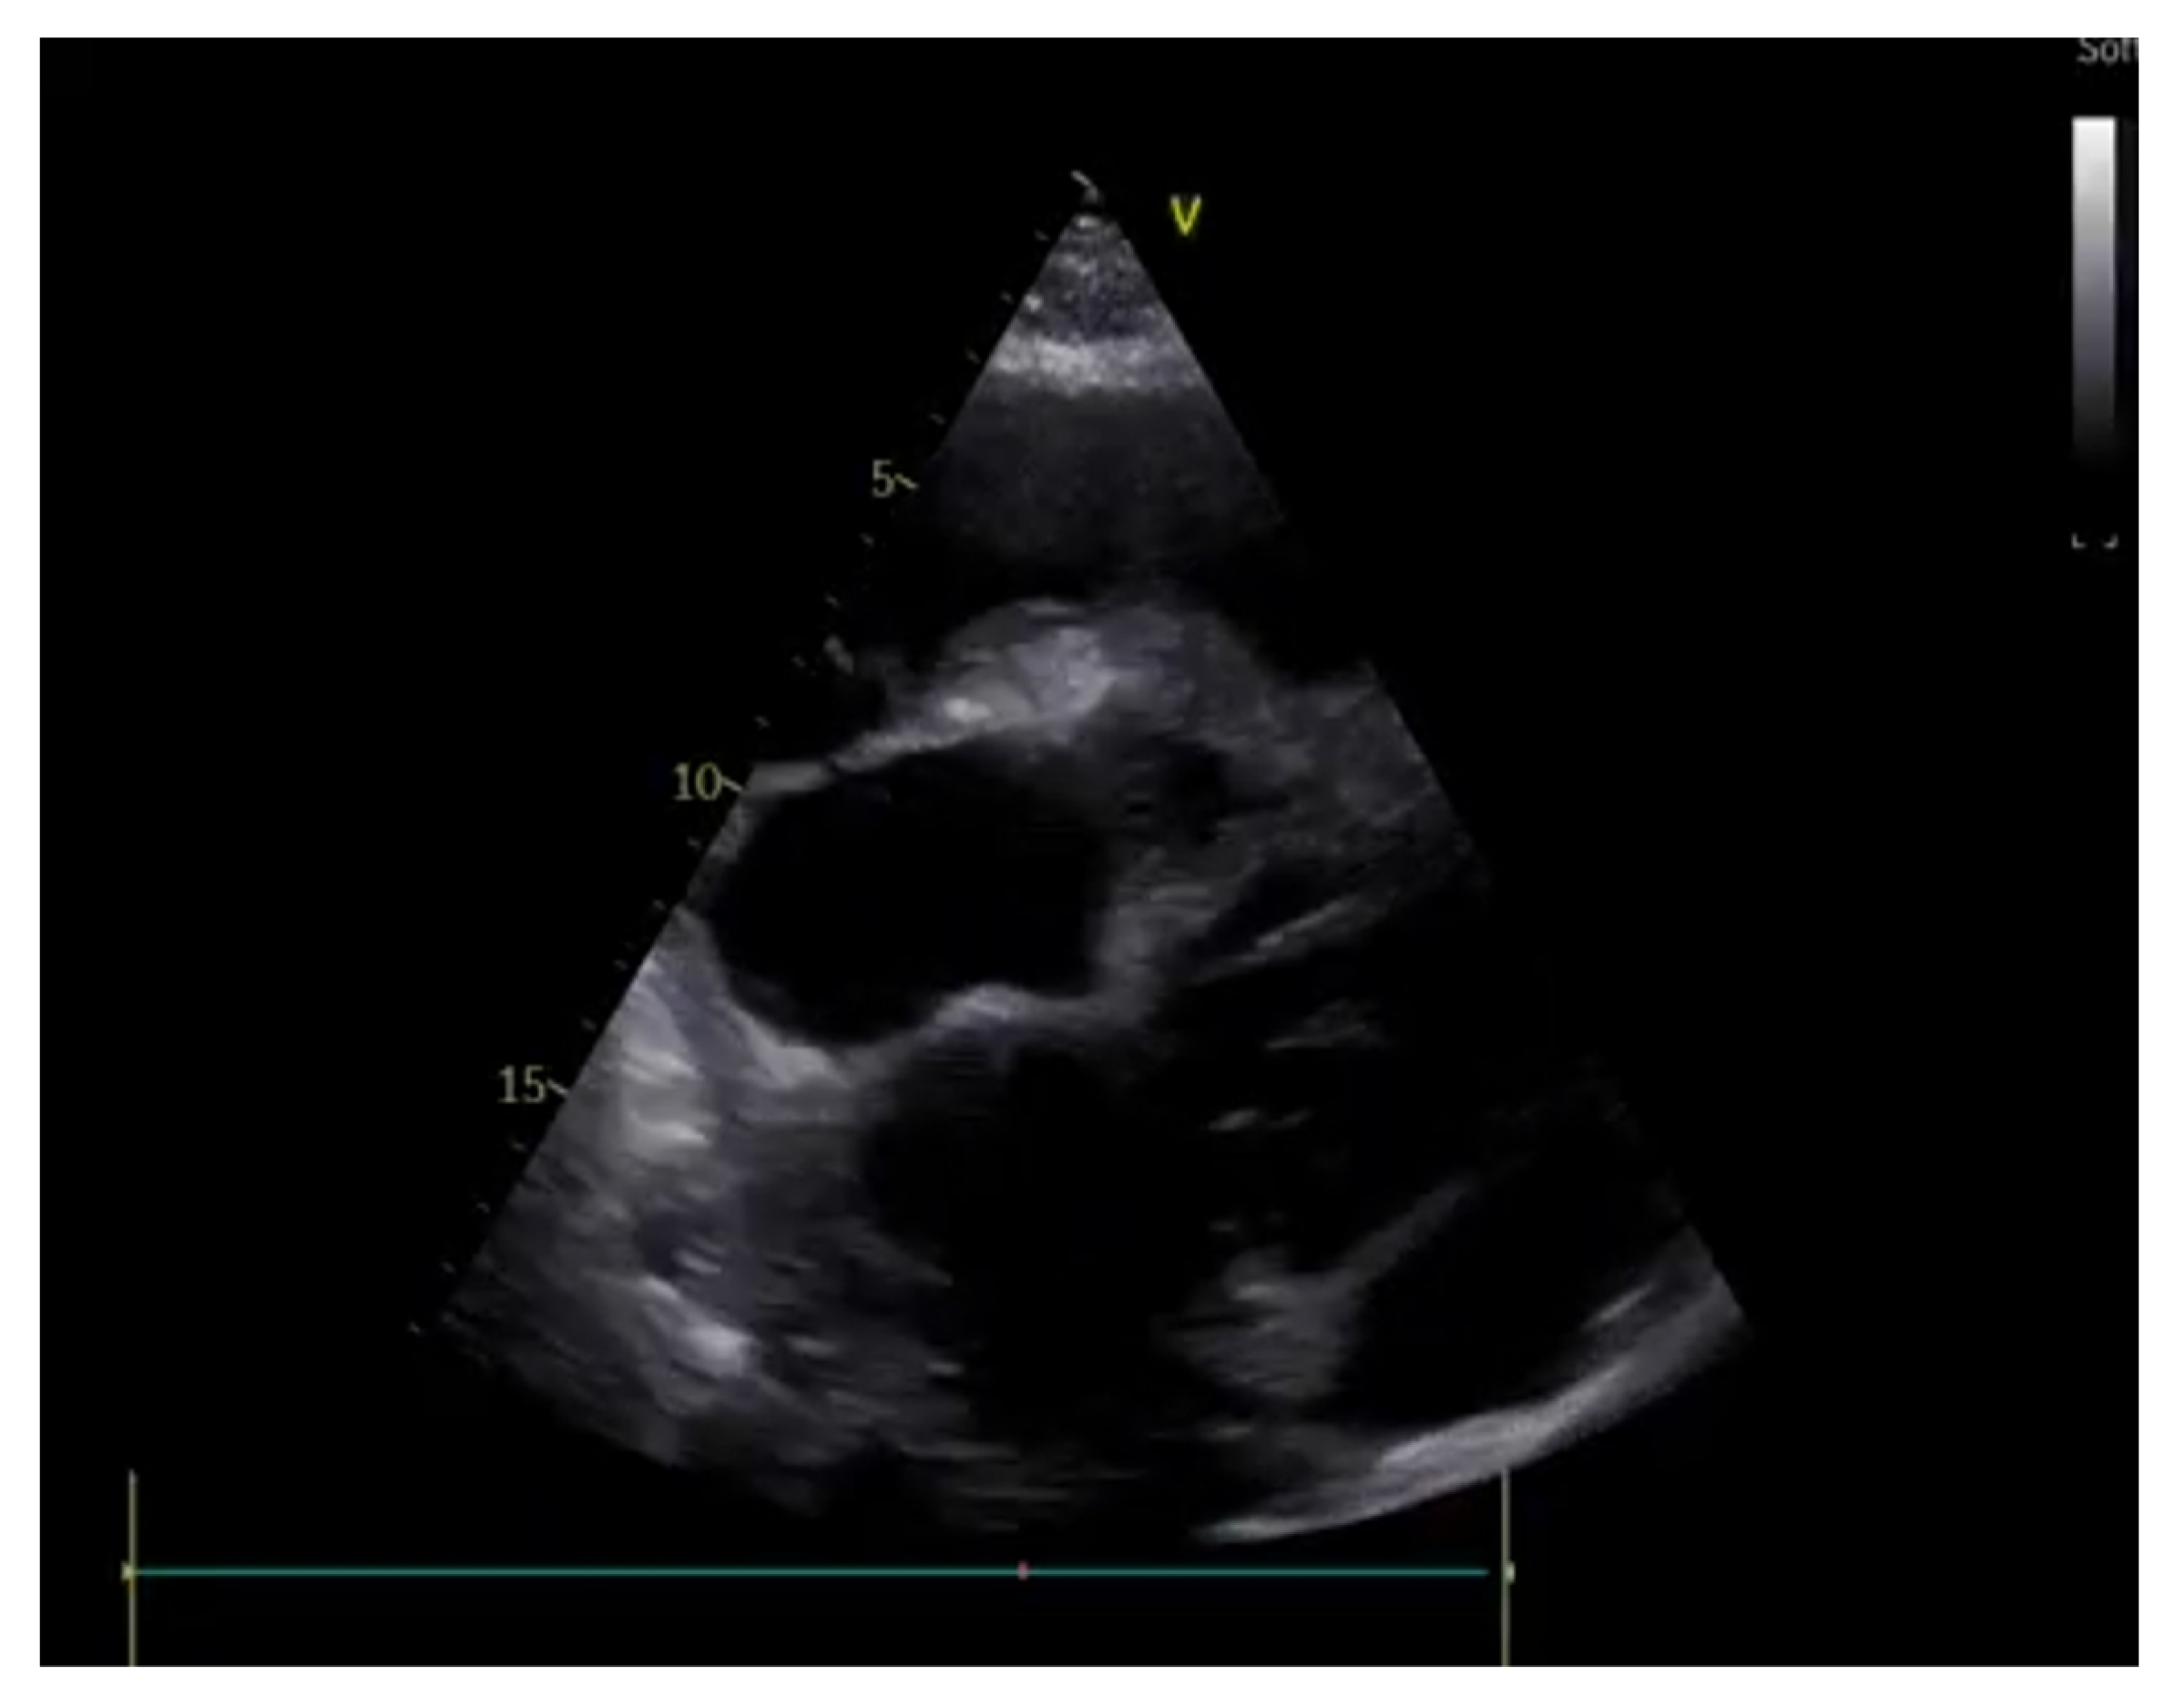

3. Cardiac Ultrasounds in the Emergency Department

3.1. Rationale and Methodology

3.2. Shock

- Cardiac chambers size and systolic function